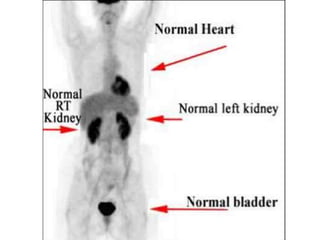

Indication for molecular imaging

• Staging of patient with distant mets

• Loco regional extent

• Response to therapy

• Restaging of patient with loco regional

recurrence/mets

• Monitoring response to therapy

• Lymph node and mets

• Dense breast

• Implants

• Localize Primary in presence of mets

• Bone metastasis

PET Imaging